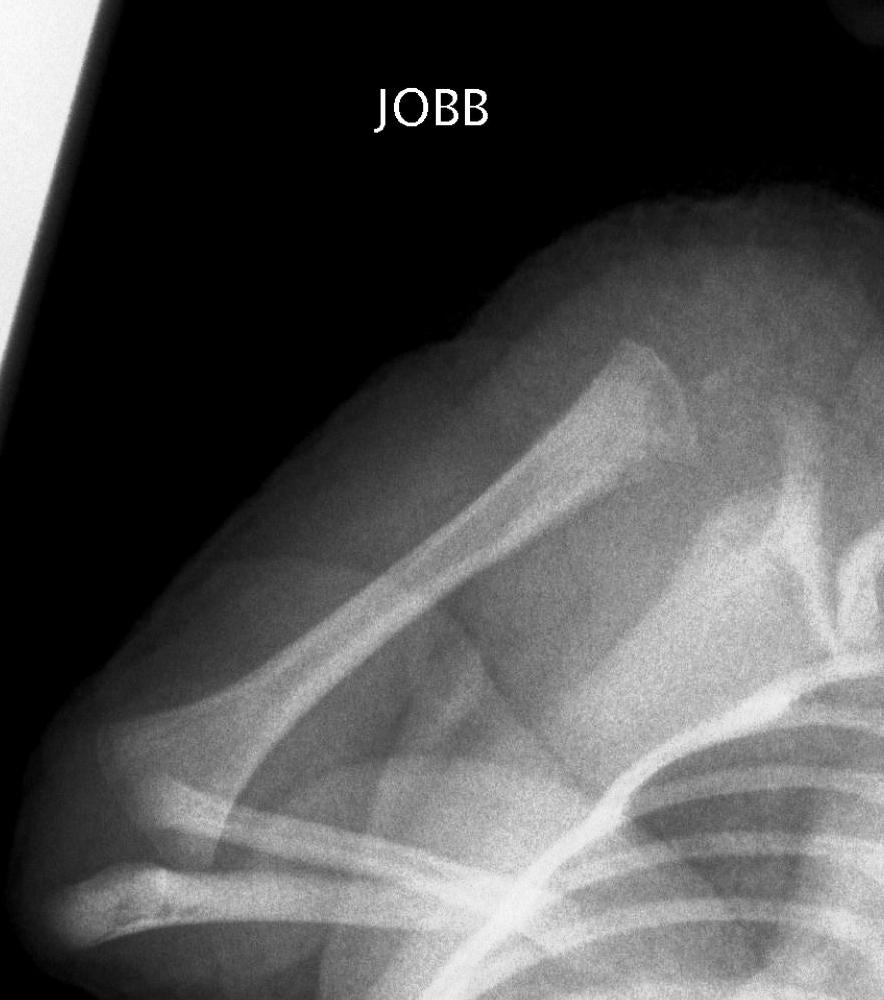

Image

37.a.

37.b.

37.c.

37.d.

37. a-d) X-ray of the right humerus. a. Rarefaction in the proximal-medial part of metaphysis of the right humerus – early osteomyelitis. b. Two weeks after the lytic area has grown. c. 1 month later sclerotic regeneration has begun. d. 4 months after almost complete healing. Osteomyelitis, infant.